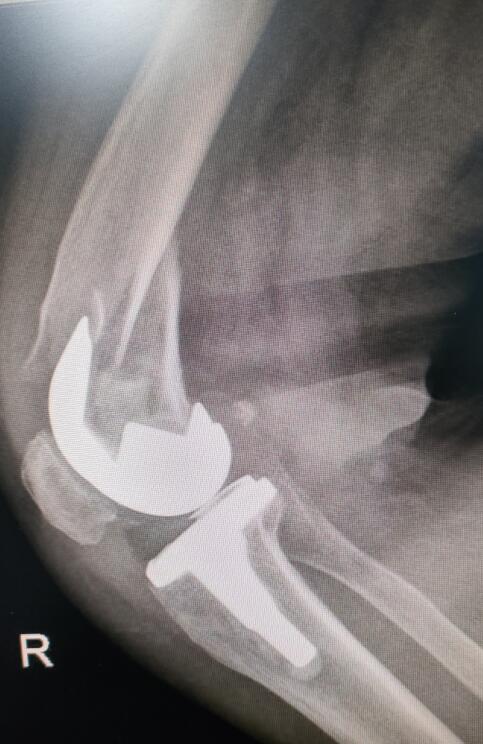

手術(shù)前照片